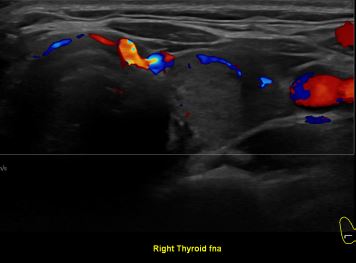

상기환자 외부건진 이상소견으로 내원하신 40대 중반 여성분으로

의심스러운 갑상선 우엽 세포검사후 갑상선암으로 진단되었습니다